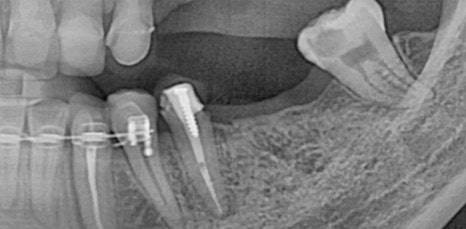

하지만 임플란트 시술을 튼튼하고 안전하게 하기 위해서는 무엇보다 잇몸뼈의 양, 두께 즉, 잇몸 상태가 매우 중요한 부분이었어요. 뿌리 역할을 하는 픽스처의 길이는 다양한 사이즈가 있지만 평균적으로 최소 8mm 이상이므로 잇몸 뼈의 길이가 8mm가 되지 않는 상태로 임플란트를 식립하게 된다면 픽스처가 잇몸을 뚫고 나가게 되어 구멍이 생기고 고정이 되기 어려웠어요. 그렇기 때문에 잇몸 뼈의 양이 부족하면 뼈 이식을 동반한 임플란트 시술이 필요했어요.

특히 위쪽 어금니 쪽이 상실 되어 임플란트 시술을 진행해야 하는데 잇몸 뼈가 부족한 상태라면 추가적으로 상악동거상술을 함께 진행해야 했어요. 상악동이란 코 양옆에 위치하고 있으며 뼈 속에 비어 있는 공기 주머니로 두개골의 무게를 줄여주는 곳이었어요. 상악동은 아주 얇은 막으로 둘러 쌓여 있으며 상악 쪽의 잇몸 뼈가 부족한 상태로 임플란트를 식립 하게 된다면 상악동 막이 찢어지거나 천공이 생길 수 있었어요.

상악동에 천공이 생기게 된다면 염증으로 인해 부작용이 생길 수 있었어요. 그렇기 때문에 환자 개개인마다 크기와 위치가 모두 다른 상악동의 위치와 잇몸 뼈의 두께를 정확히 파악하는 것이 중요했어요. 정밀 검사 후 임플란트를 식립 하기에 잇몸 뼈의 양이 부족하다는 진단이 나오게 된다면 얇은 상악동 막을 들어올려 준 후 필요한만큼의 뼈 이식을 진행해 주는 방법이 상악동거상술이었어요.

신논현역임플란트에서 말하는 상악동거상술은 치조정접근법과 측방접근법인 두가지 방법으로 진행할 수 있었어요. 남아 있는 잇몸 뼈의 양에 따라 이식 해야 하는 양이 달라지고 그로 인해 상악동에 접근 하는 방법을 기준으로 두가지 방법은 나눠 지고 있었어요. 먼저 치조정접근법은 잇몸 뼈가 4-8mm 정도 확보 되었을 때 사용하는 방법으로 치아가 상실 된 위치의 잇몸에 작은 구멍을 뚫어 준 뒤 그 구멍을 통해 상악동 막을 들어 올린 후 뼈 이식을 진행하는 방법이었어요.